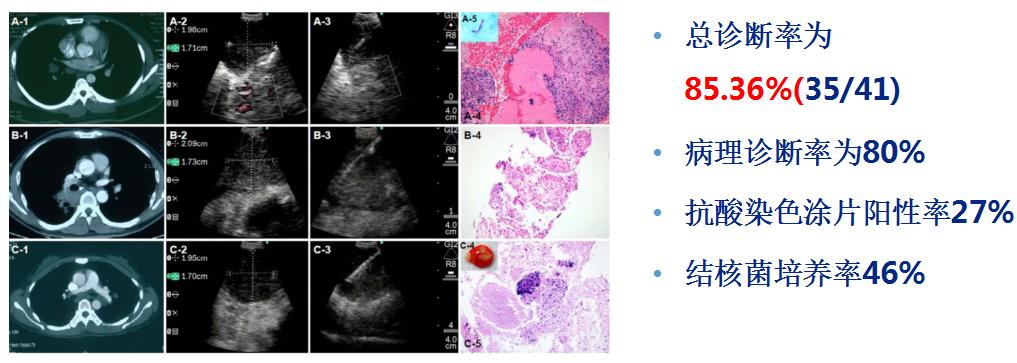

5.EBUS-TBNA诊断胸内良性疾病

(1)EBUS-TBNA诊断胸内结核

(2)EBUS-TBNA诊断结节病